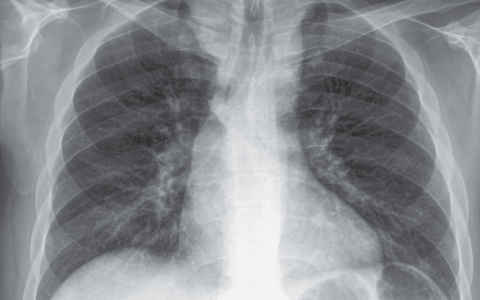

A 35-year-old man with a seven-day history of confusion(混乱), fever, chills(寒战), and cough is admitted to the hospital for evaluation. His blood pressure is 140/82 mm Hg, heart rate 108 beats/min, respiratory rate 28 breaths/min, temperature 37.9°C (100.2°F), and oxygen saturation 95% on room air. On clinical examination, he is in distress(痛苦) and can move the right upper and lower extremities but is hemiparetic(轻偏瘫) on the left. The right pupil(瞳孔) is dilated at 4 mm but reactive, and the left pupil is 2 mm and reactive. CT is shown below. He is intubated and started on IV ceftriaxone and vancomycin. His head is placed at 45 degrees, and a bolus of mannitol is administered.

这是一例继发于右侧基底神经节肿块的进行性神经功能恶化的年轻患者。他的临床表现表明即将发生疝。CT提示血管源性脑水肿,瞳孔不对称的临床检查提示腰椎穿刺可能风险太大,因为它将促进进一步向下的小脑幕切迹疝。类固醇的主要适应症是与脑肿瘤相关的血管源性水肿或伴随的脑照射和手术操作。尽管类固醇在这种模式中有益作用的确切机制尚不清楚,但类固醇降低了紧密连接通透性,进而稳定了被破坏的血脑屏障。有证据表明,治疗性低温可被认为是管理卒中和心脏骤停颅内高压的替代方法,但其用于感染性脑炎可能是有害的。可以考虑添加氨苄西林;但是,其不会对随后的小脑幕切迹疝产生任何影响。单核细胞增生李斯特菌虽然是普通人群中不常见的致病原因,但在孕妇、新生儿、老年人和免疫功能低下人群中是一种重要的病原体。